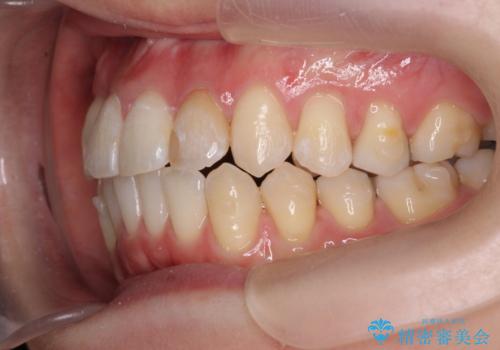

引っ込んだ前歯を並べたい マウスピースと部分ワイヤーのコンビネーション矯正

- 引っ込んで生えてしまっている前歯を並べたい、と矯正治療を希望され来院されました。

まずマウスピース矯正インビザラインシステムで、引っ込んだ歯が並ぶためのスペースを作ったのち、部分ワイヤー矯正を行い短期間での配列を計画します。

このように前歯の部分ワイヤーは引っ込んでしまった前歯や がたつきを素早く改善することができます。